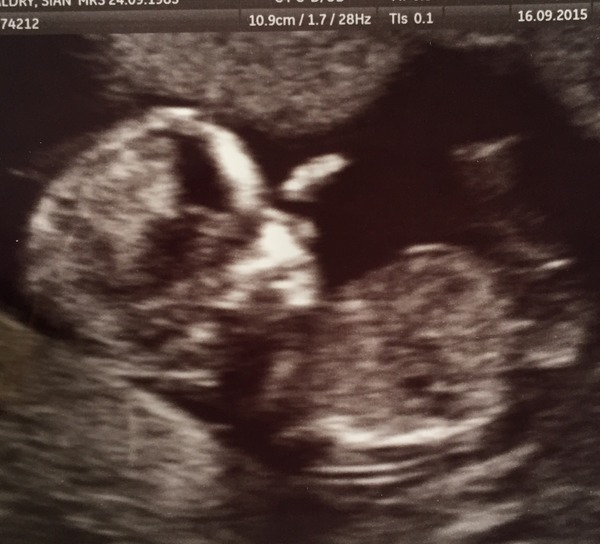

Good news from my 12w scan. All looked fine and they have dated me at 12+3 Smile

Aw brilliant scan pic fussy. Congrats.

That's a great scan photo fussy